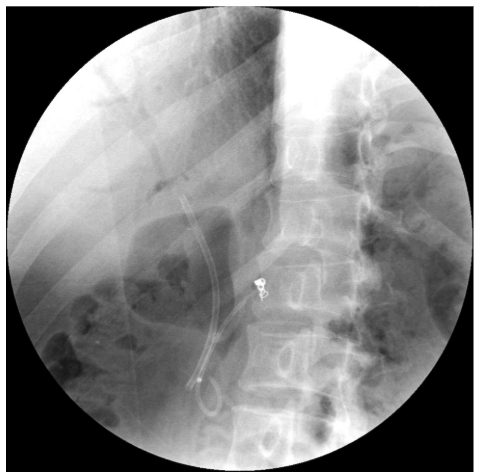

The Forgotten Biliary Stent

Pathophysiology, Surgical Retrieval, and Lavage-Related Complications